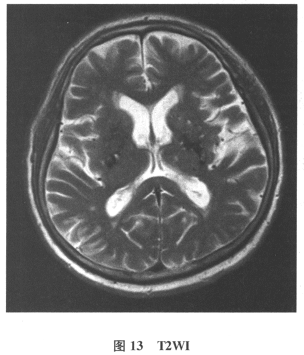

[多选题]患者男,61岁。因“发作性头晕2年,加重伴记忆力下降、走路不稳3月余”就诊。查体:BP140/70mmHg;意识清楚,构音障碍,近期记忆力及远期记忆力